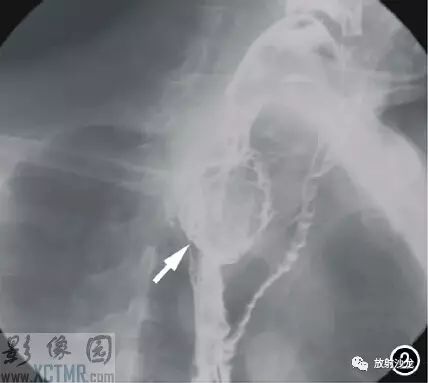

上消化道鋇餐:食管胸上段可見(jiàn)不規(guī)則充盈缺損,約5.6cm*4.2cm,黏膜結(jié)構(gòu)紊亂,管壁不規(guī)整,對(duì)比劑通過(guò)稍緩慢,會(huì)厭動(dòng)度不協(xié)調(diào),考慮食管癌(圖2)。CT:食管胸上段見(jiàn)軟組織腫塊,上自杓會(huì)厭披裂,下至主動(dòng)脈弓水平,腫塊邊緣清晰,密度均勻,增強(qiáng)掃描輕到中度不均勻強(qiáng)化,食管腔狹窄,氣管、右側(cè)甲狀腺、鄰近血管受壓移位(圖3),縱隔未見(jiàn)腫大淋巴結(jié),診斷:食管癌可能。